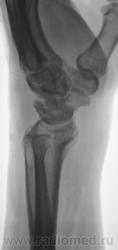

Пол пациента: Мужской пол Тип патологии: Другое Область исследования: Скелетно-мышечная система Методы исследования: Rg Пациент направлен на рентгенографию лучезапястного сустава с диагнозом - "Деформирующий артроз" Произведено стандартноы исследование. https://radiomed.ru/sites/default/files/styles/case_slider_image/public/user/12/2.DFA_..JPG?itok=Id8ocGkL ID:2136 Ср, 24/03/2010 - 18:38 #1 rentgengb1 Не на сайте Был на сайте: 11 лет 12 месяцев назад Зарегистрирован: 13.02.2009 - 23:02 Публикации: 290 Асептический некроз полулунной кости? Ср, 24/03/2010 - 19:04 #2 Катенёв Валенти... Не на сайте Был на сайте: 7 лет 3 недели назад Зарегистрирован: 22.03.2008 - 22:15 Публикации: 54876 Изображения с увеличением. Приложения: Ср, 24/03/2010 - 19:06 #3 DR.RAD Не на сайте Был на сайте: 11 лет 8 месяцев назад Зарегистрирован: 25.03.2009 - 18:22 Публикации: 805 и как следствие артроз лучезапястного сустваа... Пнд, 29/03/2010 - 00:03 #4 brainmodel Не на сайте Был на сайте: 2 месяцев 2 недели назад Зарегистрирован: 18.03.2010 - 22:04 Публикации: 2881 Болезнь Кинбека со вторичным артрозом, стадия фрагментации. Verum plus uno esse non potest.

Изображения с увеличением.

Болезнь Кинбека со вторичным артрозом, стадия фрагментации.